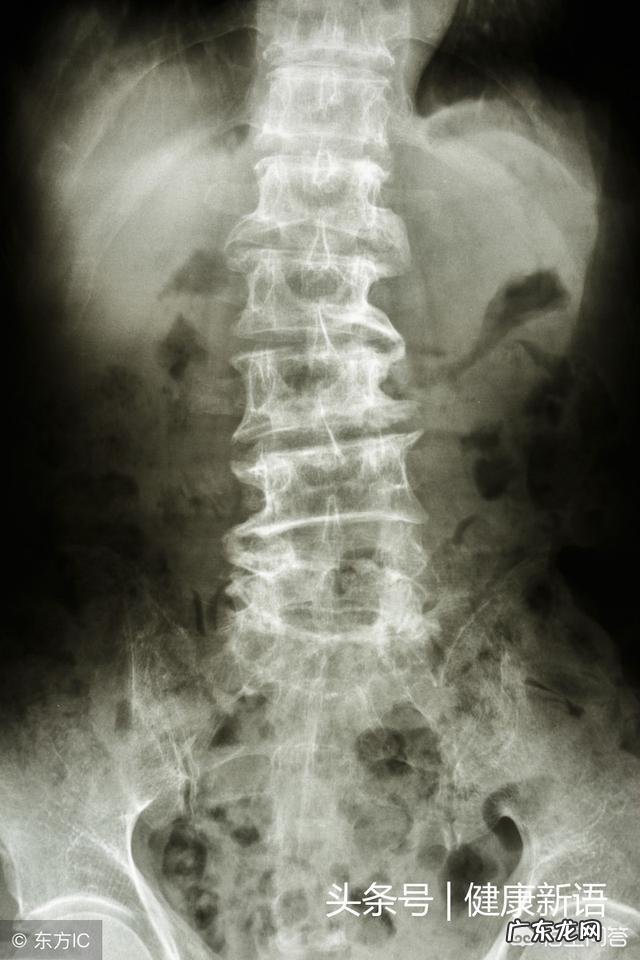

患了骨质增生、椎疼痛,该怎样zhi疗? ?诊断、诊断、诊断从来不是报告单上写的,不要由于做个检查发现什么问题,就认为是这种退变造成的症状,你问的应该是腰椎痛,做检查可能发生骨质增生,询问怎么zhi疗!

在临床中观察,多数的长期腰痛的患者中,多数伴随着骨质增生,可是在康复之后,骨质增生做检查的时候仍然可以发现,这说明一个很明确的问题,腰部的疼痛多不是骨质增生本身导致的 。

疼痛可能先于增生

那么为什么会出现骨质增生,一个是随着年龄增生,脊柱的退变,一个是长期的过度使用腰椎,还有一个原因恰是由于长期的腰部疼痛,导致骨质增生的出现,然后把他们出现的先后顺序本末倒置 。

不可都一样处理

腰椎疼痛,准确的说腰部疼痛的原因有很多,谈zhi疗的话应该先明确诊断,不同的问题导致的症状,应该采取不同的方案,如果盲目止痛,或者千篇一律的采取一样方案,康复率一定不会高

结语例如,腰肌劳损,可以通过推拿的方式来恢复劳损疼痛失去弹性的肌肉,腰椎小关节紊乱,可以通过正骨来矫正紊乱的小关节,腰椎间盘突出症可以采取手法复位的方式消除放射痛点,愿遇到对的医生!